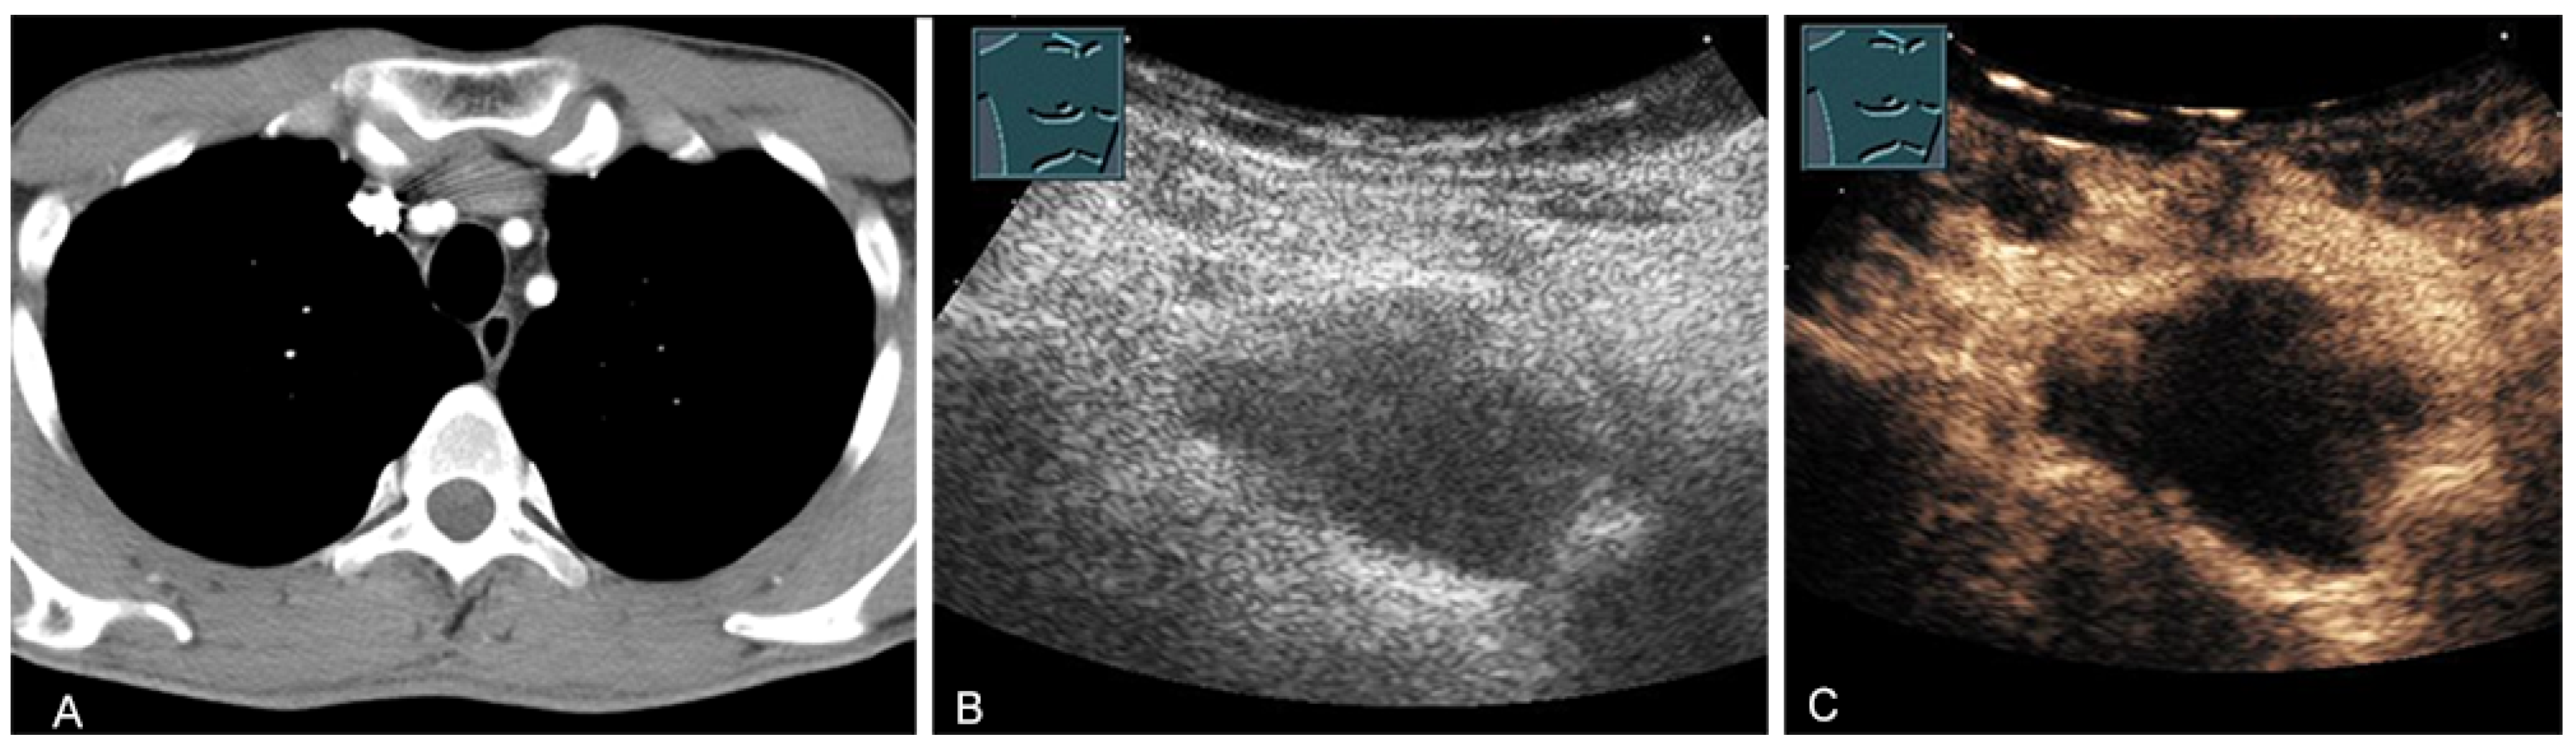

Malignant tumors of the thymus may have irregular borders with infiltrative growth, chaotic vascularization, cystic areas, or necrotic components on B-mode US, CDS, and CEUS [28,36,37]. These features can be used to evaluate the malignancy of the masses in the mediastinum. However, the definitive diagnosis is basically made by histological confirmation. More frequently, primary central bronchial carcinomas grow infiltrating directly into the anterior mediastinum and can be sonographically visualized in the case of pleural contact and, therefore, can also undergo US-guided biopsy (Figure 24).

Figure 24.

A patient with tumor formation in the anterior and middle mediastinum on CT (provided by Prof. Dr. Andreas H. Mahnken, Marburg, Germany) (A), B-mode US (B), and CEUS (C), confirmed by biopsy as primary bronchial carcinoma.

Central bronchial carcinomas can also be sonographically visualized by using the associated atelectasis as an “acoustic window” into the mediastinal processes [38] (Figure 25).

Figure 25.

A patient with mediastinal mass on CT (provided by Prof. Dr. Andreas H. Mahnken, Marburg, Germany) (A), B-mode US (B), and CEUS (C), differentiating bronchial carcinoma (TU; hypoenhancing) from downstream atelectasis (AT, marked enhancement).